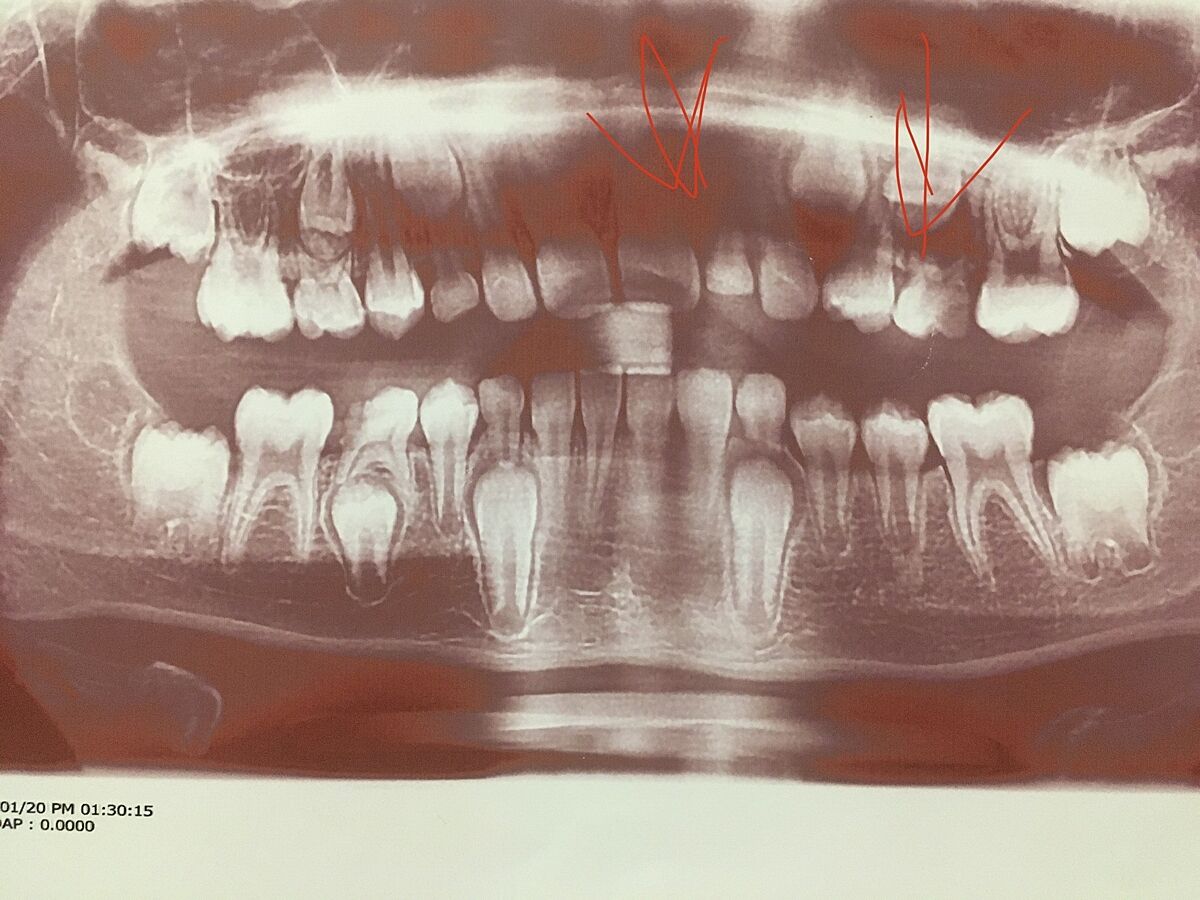

Ну для того что бы что то советовать, нужно видеть хотя бы фото или панорамный снимок. Вряд ли корпусно стала двойка прстоянная рядом с молочной, скорее всего она прорезалась щечно, но корень расположен с наклоном. Я не видела такого, что постоянная и молочная двойки паралельные.

У нас именно паралелльные. Если не снимок никто и не понял…. Разве что по форме что Этторе клык.Посмотрите пожалуйста

Видаляти двійку молочну однозначно і двигати постійну.

Ответ дляvetka

Вот я испугалась что если тянуть время то 3ка замрёт и останется в десне…. Был бы зуб подальше не трогала бы…. Как тут пишут во взрослом возрасте решали бы… но теперь новые переживания… хоть бы получилось подвинуть все ровно… а остальные зубы не пострадают от брекетов?

Тройка уже ищет себе место и может резорбировать корень двойки. Я не ортодонт, но я бы удаляла молрчну сейчас. Если будете чистить и следить за гигиеной, не пострадают.

Спасибо, 2ку удалили уже, снимок до удаления…